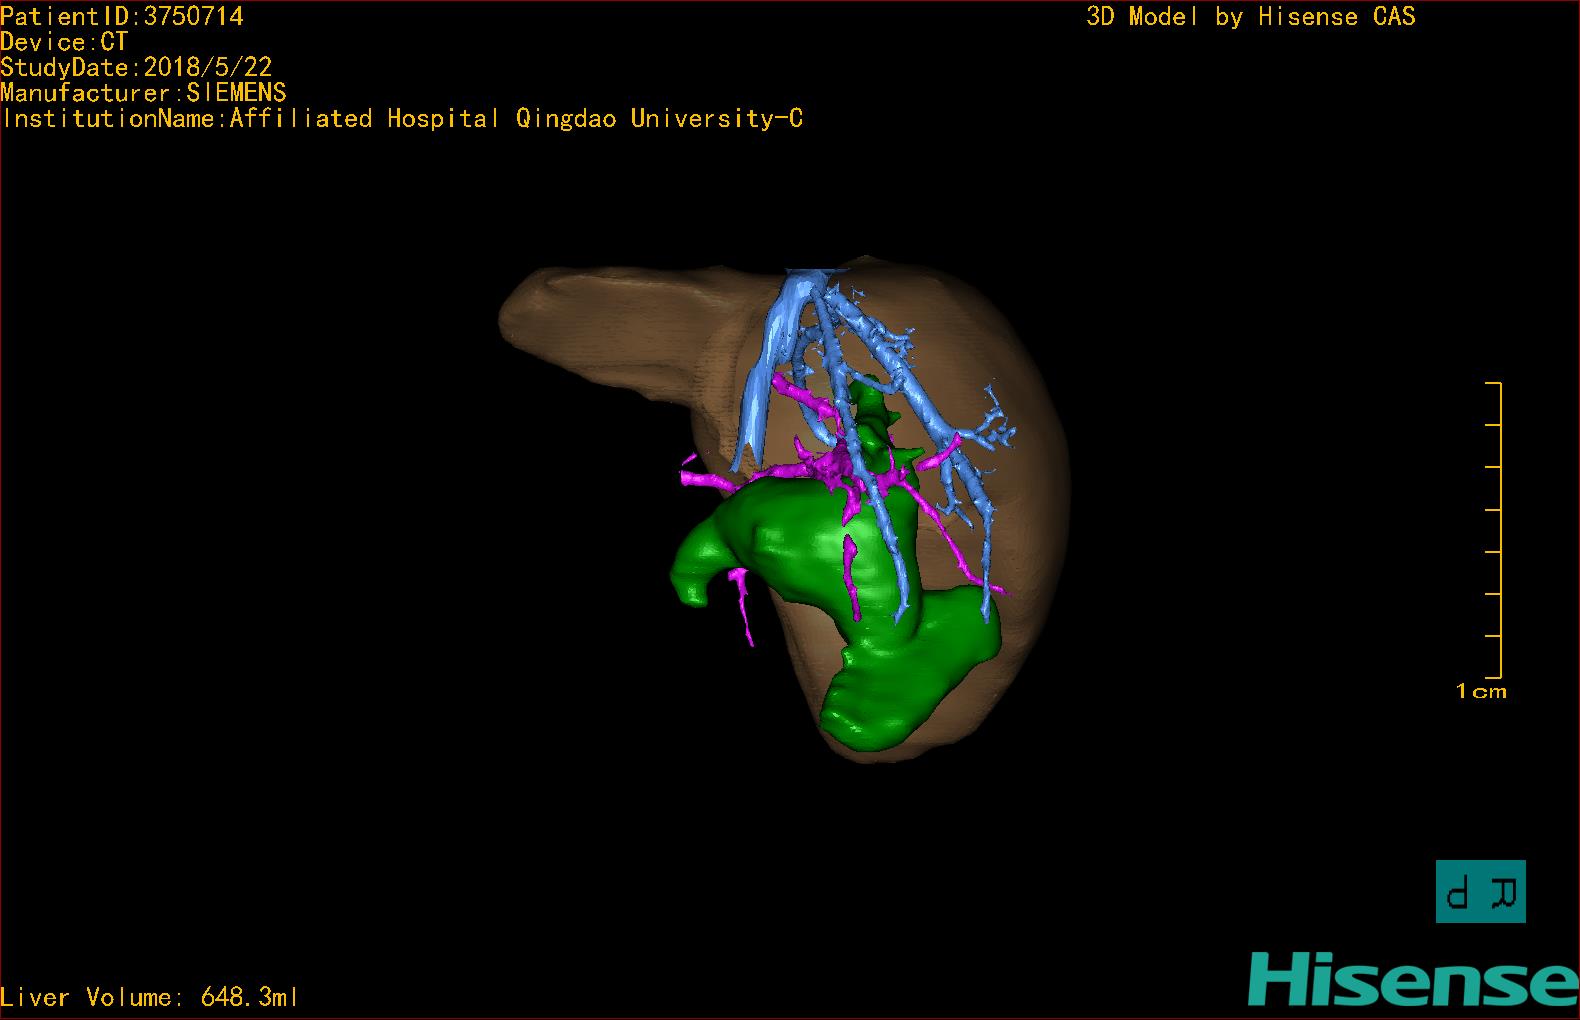

实验室检查: 血常规:WBC 16.16*109/L,NEU2.88*109/L,RBC3.76 1012/L,HB 92g/L, PLT 414*109/L 生化全套:ALT 50.00 U/L, AST 147.00 U/L, ALT/AST 0.34,LDH 367.00 U/L, ALB 36.91g/L, GGT 1297.00 U/L, ALP 1155.00 U/L, BIL-T 138.23 umol/L, BIT-D 97.01 umol/L, TBA 48.40umol/L,ADA 40.00U/L, PAB 121.40mg/L, BUN 1.98 mmol/L, CREA 17.00 umol/L 肝炎全套: 炎症反应标志物:CRP 7.27mg/l 诊疗过程: CT结果输入海信CAS系统后行3D重建及手术规划后,于2018-5-31全麻下行“胆总管囊肿切除+肝总管空肠吻合术”手术治疗: 术前三维重建及手术方案设计: 将0.625mm双源薄层CT资料的静脉期和动脉期Dicom格式文件导入海信CAS系统。 通过调节窗宽窗位调整CT序号,对肝实质,胆囊,下腔静脉,肿瘤,肝动脉、门静脉及肝静脉等进行三维重建;系统自动计算肝脏体积,肝脏体积为648.3ml,通过术前模拟手术,精准判断手术切除范围,进行精密术前规划及讨论后实施手术。 手术步骤: 麻醉成功后,患儿取平卧位,2.5%碘伏消毒手术区皮肤,铺无菌巾单。取右上腹纵口长约5m,切开皮肤、皮下织组,腹直肌前鞘、腹直肌,后鞘和腹膜。探查见:胆总管3×2cm大小,胆囊管迂曲,长约10cm。 剥离、切除胆囊,游离胆总管,将之横断:①近端即肝总管,剪裁后被吻合用;②远端游离切除囊肿内壁,直至胆总管开口于十二指肠处,冲洗后予以结扎缝扎。距treits韧带20cm处横断空肠:①近端与其远端25cm处的空肠侧壁行端侧双层吻合,吻合口通畅;②远端断端封闭,其侧壁剪开,并经横结肠后提至肝门处,与剪裁的肝总管行端侧双层吻合。缝合修补胆囊床及系膜裂孔,肝门部放置橡胶引流管一根。温盐水冲洗腹腔。检查无活动性出血,清点纱布器械无误,依次缝合腹壁各层。手术顺利,麻醉满意,出血不多,未输血,术后病人先进入麻醉恢复室,苏醒后回病房。手术时术者可开启Hisense CAS系统手势控制功能,对肝脏及胆囊解剖结构进行实时、全方观察、评估,起到术中导航作用。 术后病理: 1. (囊肿壁)囊肿性病变,囊壁部分区域衬覆柱状上皮。 2. 慢性胆囊炎。 3. 送检(肝门)淋巴结查见淋巴结1枚,呈反应性增生。 随访情况: 患儿术后2周恢复良好 术前CT检查:动脉期

术前三维重建:重建图片.jpg)

.jpg)